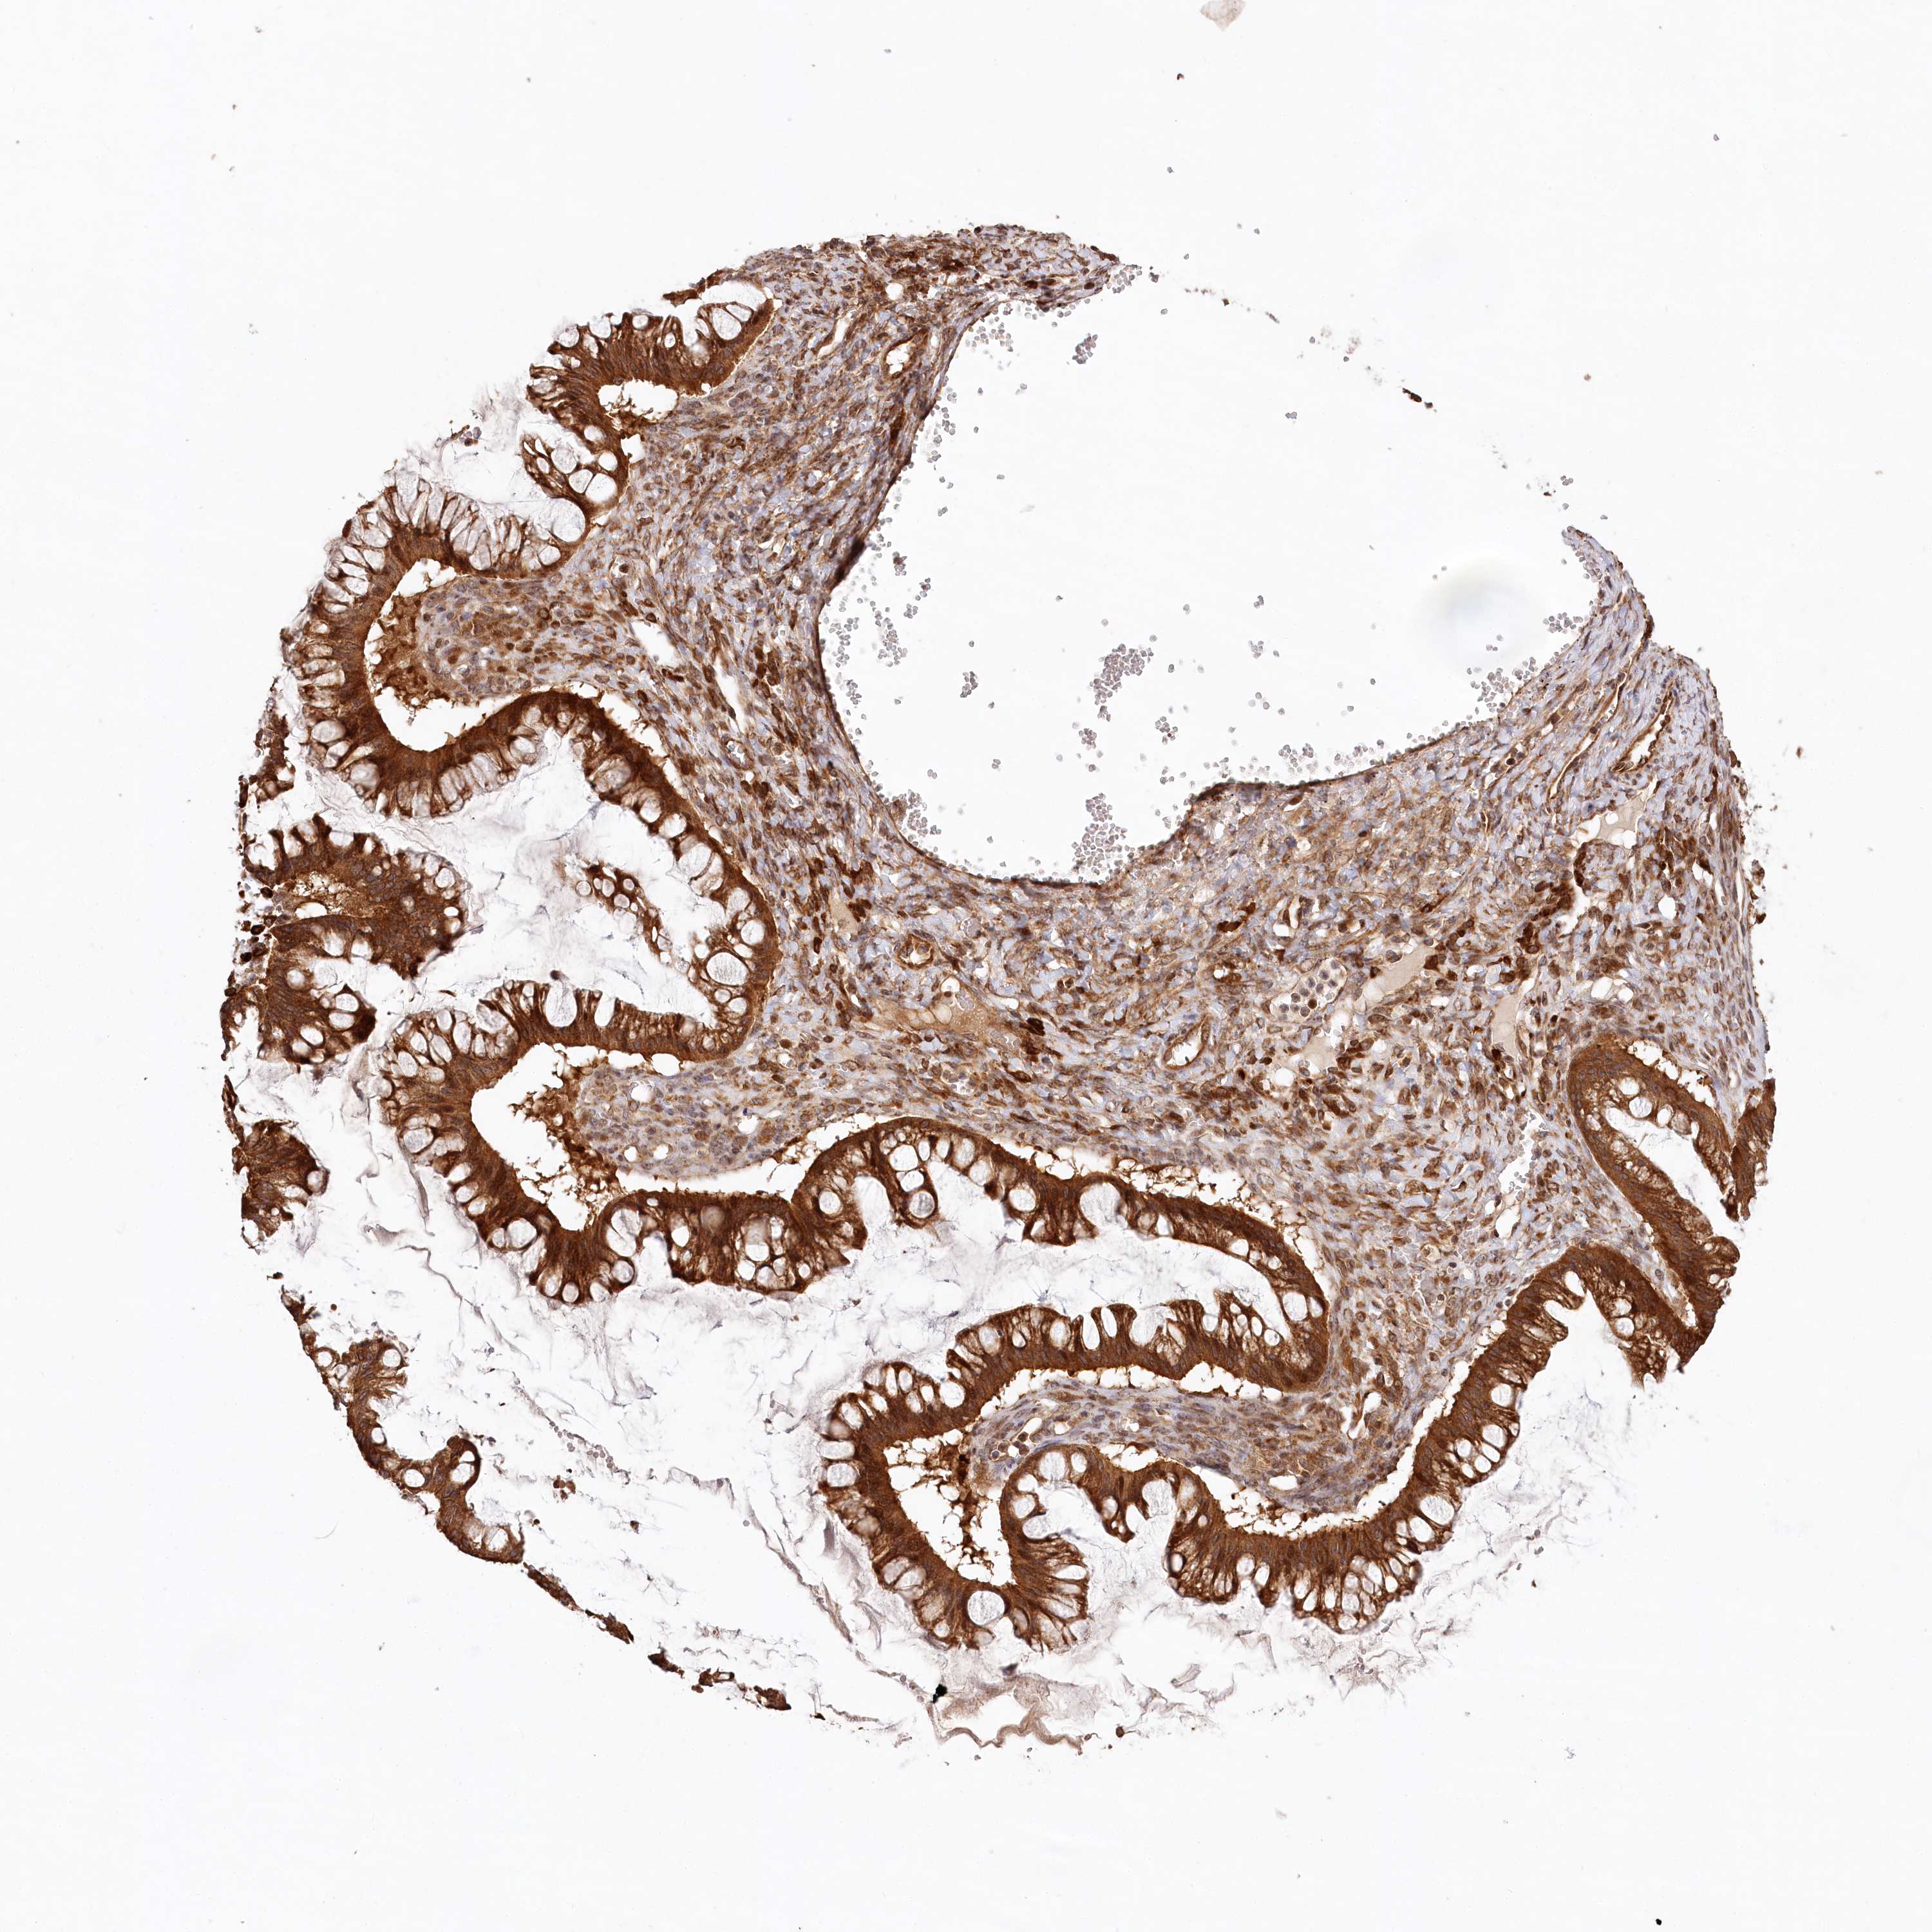

OVARIAN CANCER - Protein expressioni

A mouse-over function shows sample information and annotation data. Click on an image to view it in a full screen mode. Samples can be filtered based on level of antibody staining by selecting one or several of the following categories: high, medium, low and not detected. The assay and annotation is described here.

Note that samples used for immunohistochemistry by the Human Protein Atlas do not correspond to samples in the TCGA dataset.

Antibody stainingi

Antibody staining in the annotated cell types in the current human tissue is reported as not detected, low, medium, or high, based on conventional immunohistochemistry profiling in selected tissues. This score is based on the combination of the staining intensity and fraction of stained cells.

Each image is clickable and will lead to virtual microscopy that enables deeper exploration of all samples and also displays staining intensity scores, fraction scores and subcellular localization as well as patient and tissue information for each sample.

Antibody HPA032062

Staining

High

Intensity

Strong

Quantity

Location

Cytoplasmic/membranous

Cystadenocarcinoma, serous, NOS